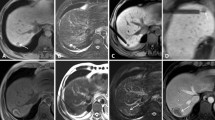

a After energy application to the lesion in segment V, a T1 hyperintense region can be seen around the two hypointense tips of the applicators which were crossed orthogonally during that slice. T1 hypointense tissue is still visible ventral and dorsal to the applicators corresponding to viable tumour (arrowheads). Two ablation zones from previous RF therapies are located in liver segment VIII and VII; a viable lesion can be seen in segment VI. b On a coronal image, the initial tumour (arrowhead) can be differentiated as a hypointense area within the hyperintense ablation zone after retracting the applicators. As it is surrounded by a T1 hyperintense rim, it can be interpreted as a treated, non-viable lesion. c After repositioning the probes and further ablation, the ventral and dorsal portions of the tumour are also ablated. d Transversal image before definitive retraction of the applicators shows a sufficient safety margin around the tumour

Technical success was assessed on the basis of the control examination performed directly post-interventional in the wide-bore 1.5-T system. Depending on the initial signal behaviour of the lesion, the intervention was classified as technically successful if no remaining tumour tissue was detected. The late phase of the contrast-enhanced dynamic liver study was used as a gold standard for evaluating the ablation zone [26]. The ablation zone should be non-enhancing and without nodular contrast enhancement at its edges, which would be signs of remaining tumour tissue. The presence (or absence) of a minimal safety margin of at least 5 mm in all directions was stated in the clinical report. A lack of safety margin was not classified as a technical failure. The same criteria were used for evaluating local tumour progression in the follow-up imaging. Residual tumour was defined as evidence of tumour tissue adjacent to the ablation zone in the control examination 1 month after therapy. Technique effectiveness was defined as complete ablation 1 month after therapy (Fig. 4). Local tumour progression was defined as evidence of vital tumour tissue adjacent to the ablation zone in the subsequent examinations [27].

Technique effectiveness was assessed using a dynamic liver examination 1 month after the intervention. A flow chart illustrates the patients’ treatment (Fig. 5). Complete tumour ablation was achieved in 210/213 (98.6 %) lesions. In three patients, treatment could not be completed (see “Technical success”).

The mean follow-up period was 24.2 months (range 6–44 months). During the follow-up, 18 cases of local tumour progression were observed (18/210), which corresponds to a local tumour progression rate of 8.6 % and to a technical efficacy of 91.4 % (Table 2, Fig. 6). Among these 18 local tumour progressions, 13 lesions were colorectal cancer liver metastasis, 2 lesions were metastases of cholangiocellular carcinoma, 1 lesion was a metastasis of breast cancer and another lesion was from bronchial carcinoma. One case of local tumour progression was observed after RF ablation of a hepatocellular carcinoma. Local tumour progression rate was 17/170 (10.0 %) for all metastases treated, 13/114 (11.4 %) for colorectal liver metastases and 1/43 (2.3 %) for hepatocellular carcinomas. The difference between colorectal liver metastases and hepatocellular carcinomas was not significant (P = 0.08) with regard to the local progression rate. Mean duration between RF ablation and detection of local tumour progression was 11.7 ± 6.4 months. The earliest detection of local tumour progression was 4 months after therapy, and the latest was 28 months. The mean initial size of the lesions with local tumour progression was 20.6 ± 8.4 mm. The mean largest ablation zone diameter in these lesions was 44.2 ± 11.7 mm and the mean smallest diameter of the ablation zone was 32.9 ± 7.2 mm. In three of the lesions, the safety margin had initially been classified as insufficient. All local tumour progressions appeared at the outer edge of the ablation zone.

a 69-year-old male patient presenting with a singular metastasis of a resected extrahepatic cholangiocellular carcinoma in segment IV with a diameter of 22 mm. b One month after RF ablation, the non-enhancing zone was classified as completely ablated. c Seven months after therapy, a multifocal local tumour progression was detected in the T1- and T2-weighted d sequences and the diffusion-weighted imaging e, whereas it was more difficult to detect the local tumour progression in the dynamic liver examination f